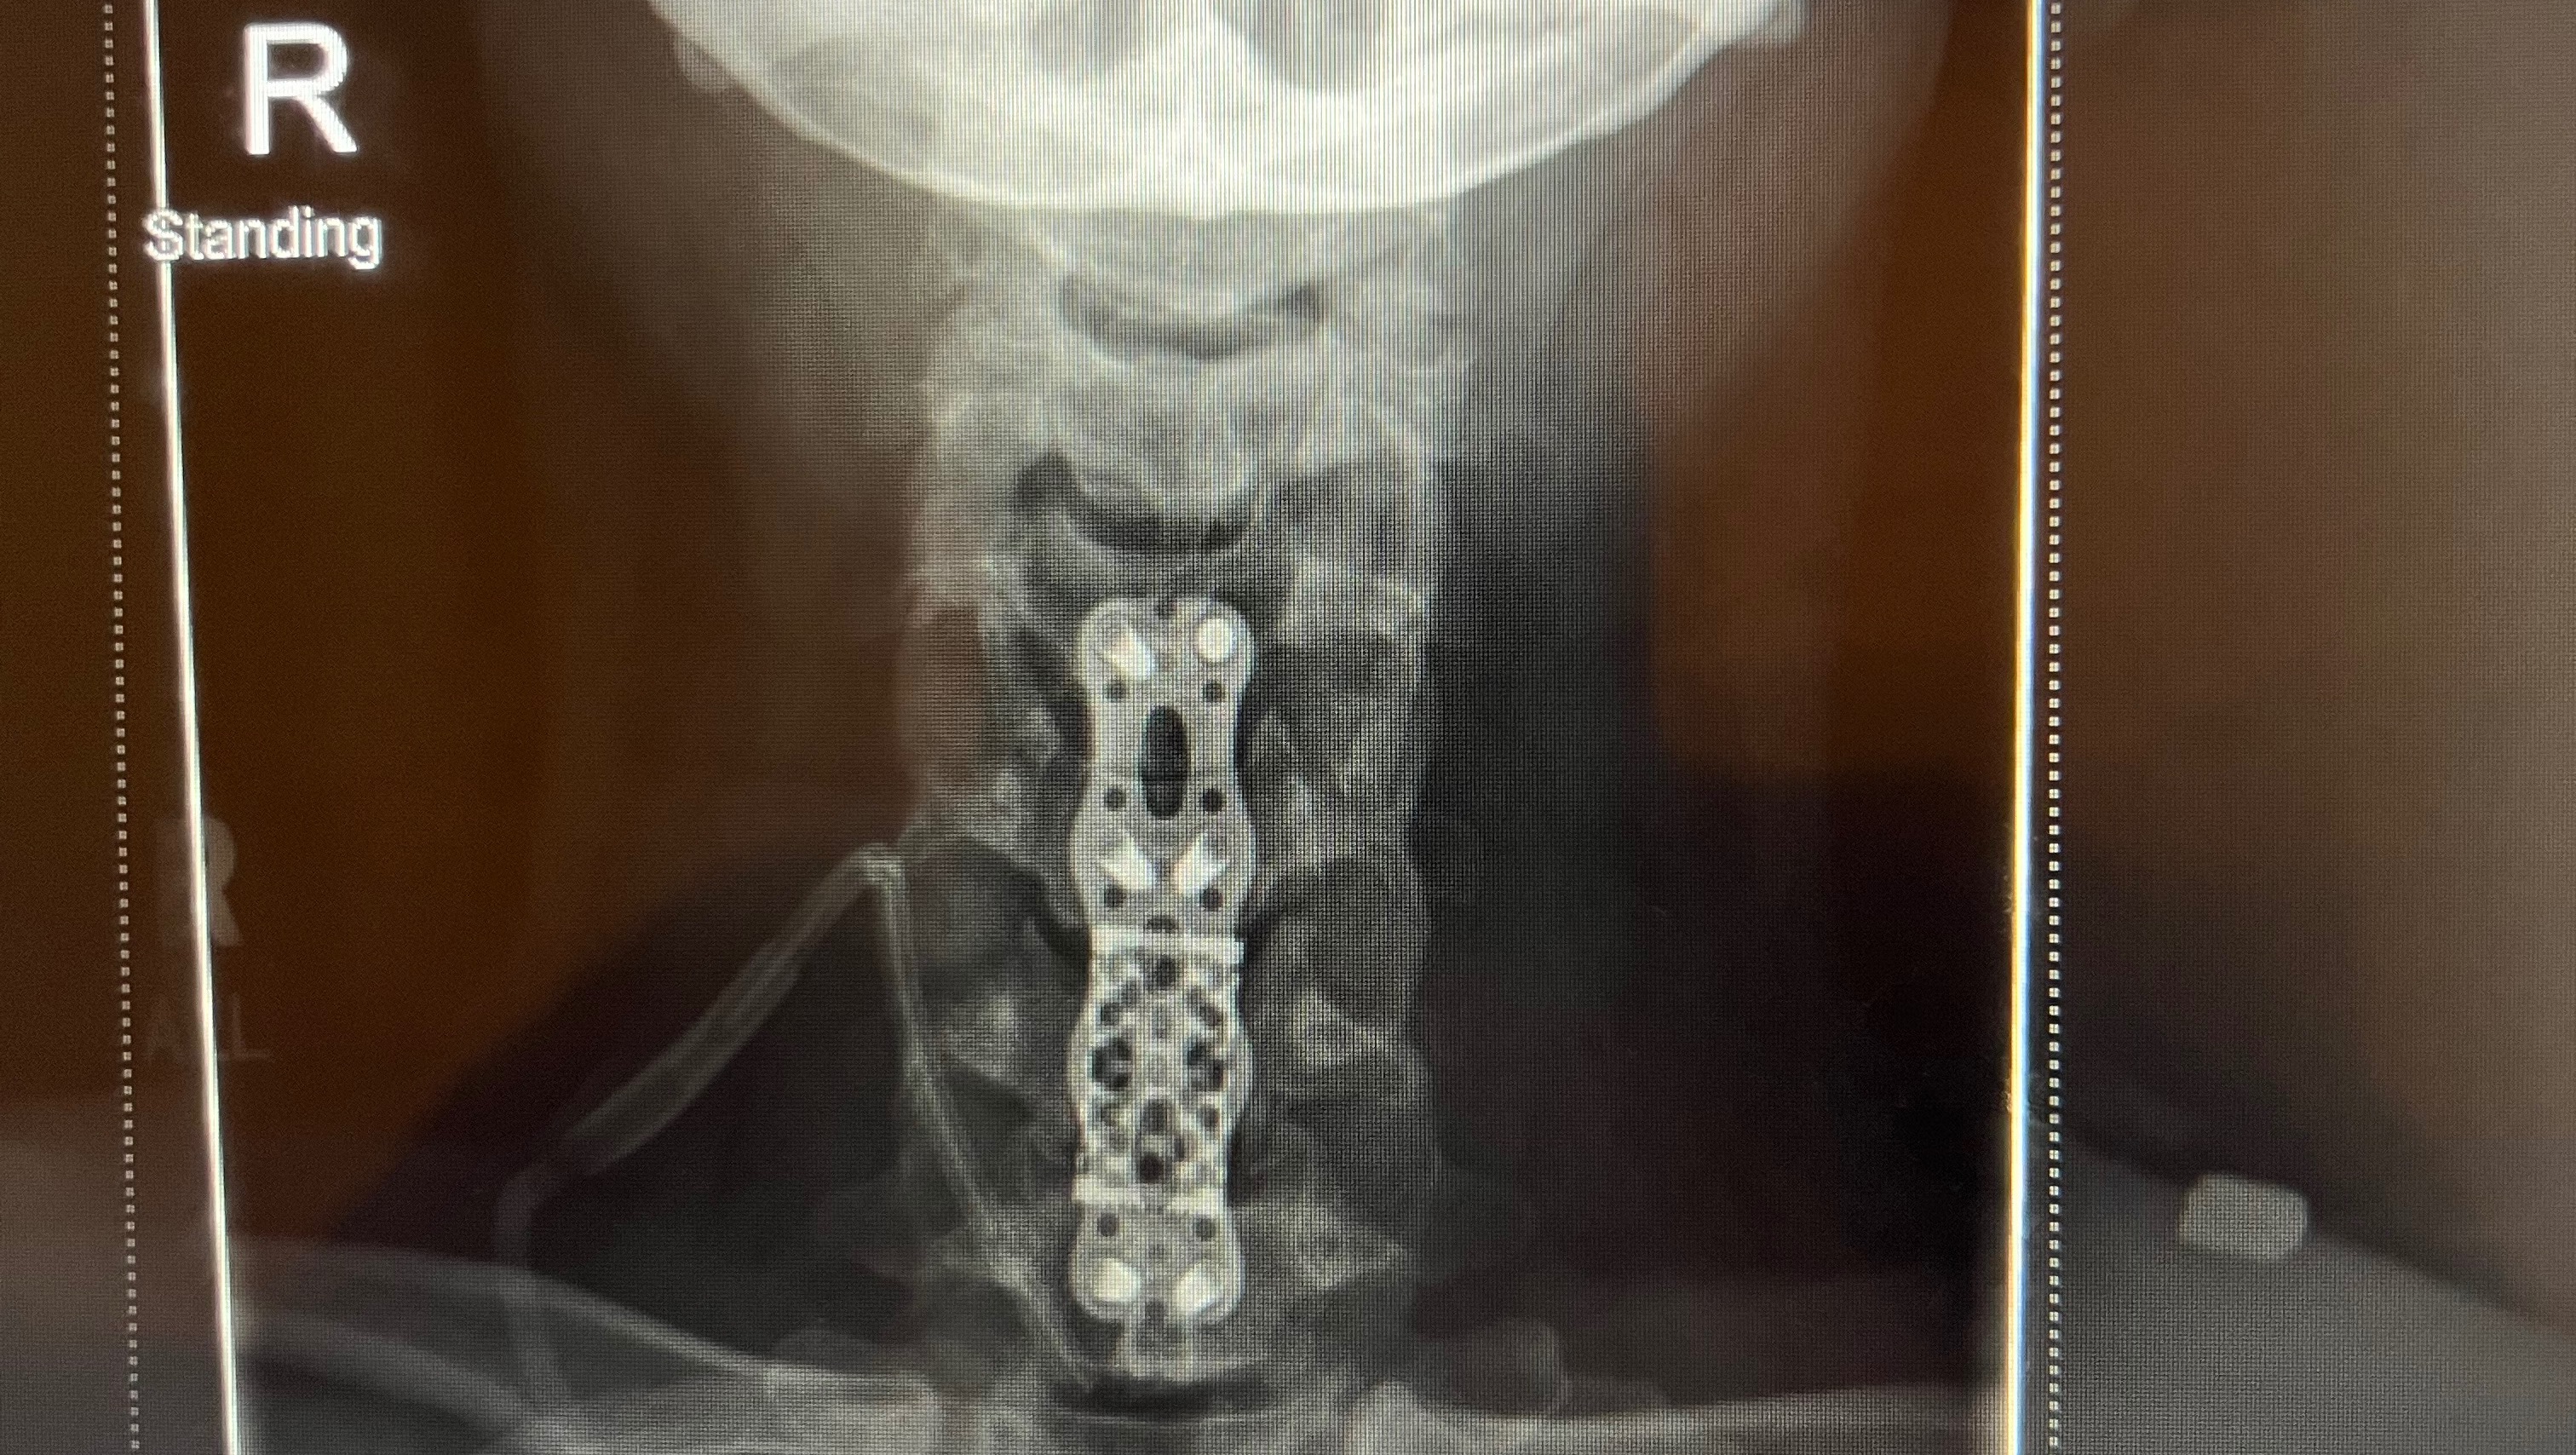

The day after Thanksgiving, Liz underwent an “anterior cervical discectomy & fusion” surgery on vertebrae C4-C7. C6 was removed, replaced with a cage, and the entirety was fused together with a supportive brace. This whole procedure was conducted through an incision on the front of her neck! Her recovery will be long, but she’s been in high spirits and doing everything she can for a smooth and speedy recovery. Though this recent diagnosis and emergency surgery has proven physically and emotionally taxing, it validates Liz’s long-felt pain from this invisible, but very real condition. Because of her illness, and imaging of her lumbar and thoracic spine, doctors have prepared her for the possibility of future, similar surgeries. She will continue her recovery by working with her physical therapists, occupational therapists, a nutritionist, naturopath, spinal specialists, and pain specialist, along with others.